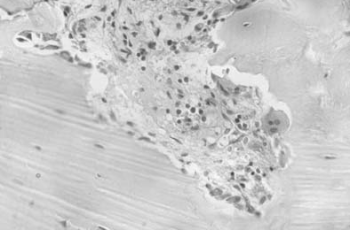

54.1.2. A csontok Paget-kórja